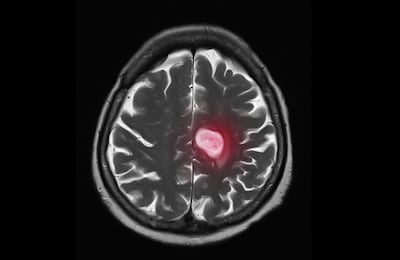

El CNIO ha valorado la importancia del descubrimiento, ya que aproximadamente un 30 por ciento de los pacientes de cáncer (especialmente los de mama, pulmón, piel, colon y recto) acaban desarrollando metástasis en el cerebro, y actualmente es una necesidad médica no cubierta porque no hay tratamientos específicos, más allá de la radioterapia y la cirugía.